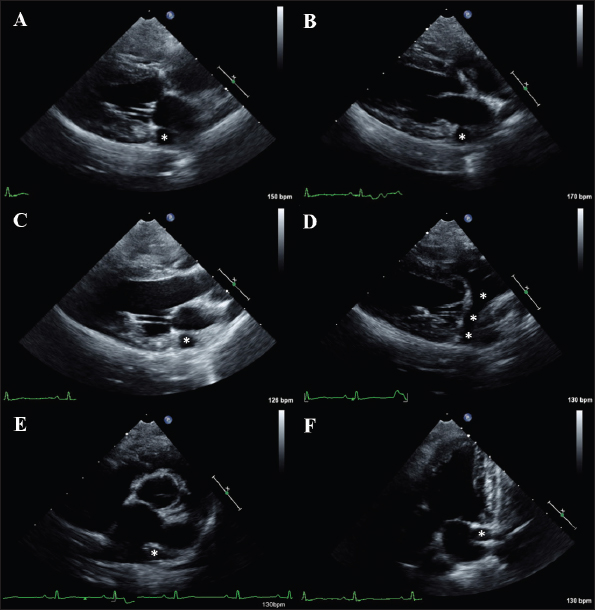

The study sample included 86 apparently healthy Pugs. Thirty-six were females (30 entire and 6 spayed) and 50 males (40 entire and 10 castrated). The median age and BW were 8 years (1–16 years) and 8.1 kg (3–13 kg), respectively. The RIs for the echocardiographic variables included in the study are reported in Table 1. The investigation of outliers revealed outlier dogs for LVDd (i.e., a value of 36.7), LVDdn (i.e., a value of 1.86 and one of 2.01), ESV (i.e., a value of 18 ml/m2), and ESVI (i.e., a value of 41 ml/m2 and one of 44 ml/m2). Since echocardiography did not reveal any pathological sign and the aforesaid values were not the results of erroneous measurements, they were not excluded from the determination of echocardiographic values. As shown in Table 2, a statistically significant effect of BW, age, and sex was observed for 7, 13, and 3 variables, respectively. In 24/86 (27.9%) dogs, a trivial pulmonary regurgitation (i.e., a barely detectable jet of a few discrete color pixels on the ventricular side of the valvular coaptation point that persists for a brief time in diastole) was found. Moreover, based on the combination of 2D and Doppler findings, a persistent left cranial vena cava (PLCVC) was suspected in 4/86 (4.7%) dogs. Such a suspect relied on the identification of an accessory vascular structure at the level of the LA lateral wall that clearly entered a subjectively mildly dilated coronary sinus to reach the right atrium (de Fornel et al., 2001; Gonzalez-Juanatey et al., 2004) (Fig. 1). The inter-observer measurement variability was low for the M-Mode and 2D variables, with CV values always below 16%. The inter-observed measurement variability was very low for Doppler variables, with CV values always below 5%.

Fig. 1. Two-dimensional images of a Pug from the present study showing echocardiographic signs consistent with a PLCVC. (A) Echocardiographic image obtained from a right parasternal four-chamber long-axis view in systole. (B) Echocardiographic image obtained from a right parasternal four-chamber long-axis view in diastole. (C) Echocardiographic image obtained from a right parasternal five-chamber view. (D) Echocardiographic image obtained from an oblique right parasternal four-chamber long-axis view optimized to observe the longitudinal section of the PLCVC. (E). Echocardiographic image obtained from a right parasternal short-axis view at the level of the aortic root. (F) Echocardiographic image obtained from a left parasternal five-chamber view. In panels (A–F), it is possible to observe the transverse section of the PLCVC. Note this accessory vascular structure appears as a round, anechoic structure adjacent to the lateral LA wall (white asterisks). In panel (D), the optimized view allows to follow the PLCVC along its course. Note that the accessory vessel enters a subjectively mildly dilated coronary sinus to reach the right atrium (with asterisks).

A last intriguing finding from this study concerns the identification of echocardiographic signs typical for PLCVC in 4/86 (4.7%) dogs. Indeed, in these dogs, an accessory vascular structure adjacent to the LA lateral wall that entered a subjectively mildly dilated coronary sinus to reach the right atrium was documented. The coronary sinus is the main cardiac vein and normally opens in the right atrium between the caudal vena opening and the tricuspid valve. The dilation of the coronary sinus always raises the suspicion of PLCVC, as, normally, the coronary sinus is not identified via echocardiography. It is important to consider that the dilation of the coronary sinus is not an exclusive feature of the PLCVC. The list of differential diagnoses for this echocardiographic finding includes conditions leading to a pathological increase in right atrial pressure (e.g., pulmonary hypertension/stenosis). However, when the aforesaid echocardiographic signs are detected in a healthy patient with an otherwise normal heart, the PLCVC represents the main differential diagnosis (de Fornel et al., 2001; Gonzalez-Juanatey et al., 2004). The PLCVC derives from a failure of the obliteration of the left anterior cardinal vein and is usually an incidental finding in dogs (Buchanan, 1963; de Fornel et al., 2001; Choi et al., 2016). When this accessory vascular structure drains into the right atrium and is not associated with additional cardiac abnormalities (as in the cases described herein), no hemodynamic consequences are expected (this explains why we decided to maintain Pugs with suspected PLCVC among healthy dogs for RI analysis). Therefore, the life quality and life expectancy are typically not influenced by this heart malformation when it is isolated (de Fornel et al., 2011; Choi et al., 2016). In dogs, a breed predisposition has previously been suspected for the Shi-tzu (Choi et al., 2016); however, no prior studies have hypothesized a predisposition to PLCVC in Pugs.